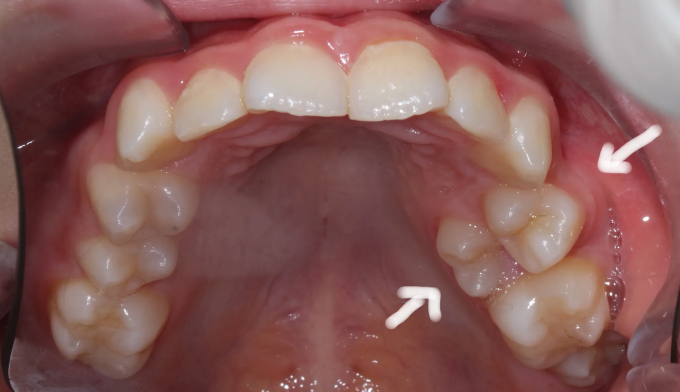

입천장치아

위 작은어금니가 겹쳐져서 맹출하였습니다.

유치를 발치할때 잘못된 순서로 발치하게 되는 경우 이런 경우가 발생할 수 있습니다.

유치 발치 후 영구치가 맹출할 공간을 확보해주어야 위와 같은 일이 생기지 않습니다.

공간이 부족하므로 먼저 양쪽으로 치아를 벌려 공간을 확보해준 후 겹쳐진 치아들을 배열해줍니다.